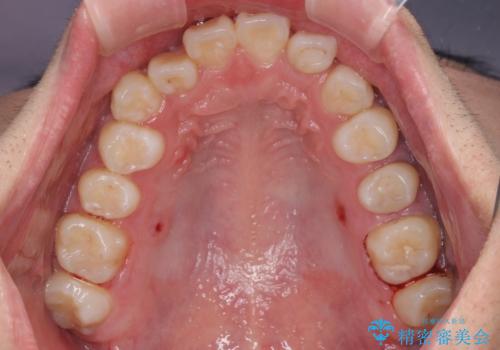

- 八重歯を気にして来院された高校生の患者様です。

ボディーコンタクトの激しい部活動を行っているため、補助装置とインビザラインを用いて、部活動を継続しながら治療を行うこととしました。

八重歯を効率よく改善するため、補助装置を使用して上顎の奥歯を後方に移動させました。

部活動をしながらでしたが、マウスピースをしっかりと装着してくださったので、1年半程度で終了することができました。